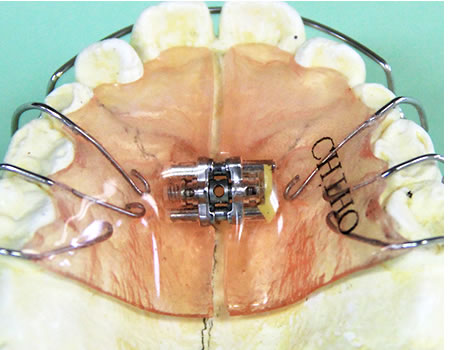

床矯正装置

「床矯正装置」とは、取り外し可能な矯正装置のことです。

口の裏側に付けるプラスチック製の床部分(レジン床)と表側の歯を抑える金属線でつくられたもので、入れ歯のような形をしています。